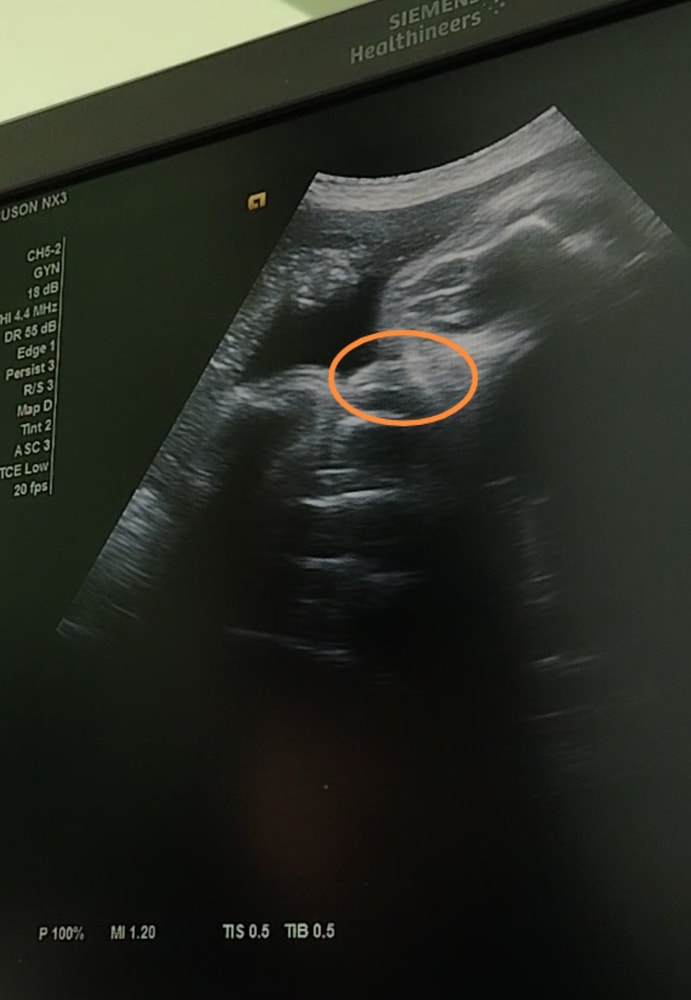

Затрудняюсь с категориейДевочки как думаете, у девочки могут так свисать из ягодиц половые губы🤔? На втором скрининге, на современном аппарате сказали 100% девочка, в 33 и 37 недель сказали что больше теперь на кукушата похожи, пол плохо видно, ещё пуповиной всё перекрыто. Как на Ваш взгляд девочка или мальчик?

Алёна Хаустова, а на этом стоп кадре🤗? Это могут быть тоже половые губы🙂

Ирина Лапина, похоже на губы,просто изображение на узи плывёт, сложно чётко зафиксировать)

Эльза, а на этом стоп кадре вроде как писюн вверх к мочевому задран, или это такие половые губы🤔?